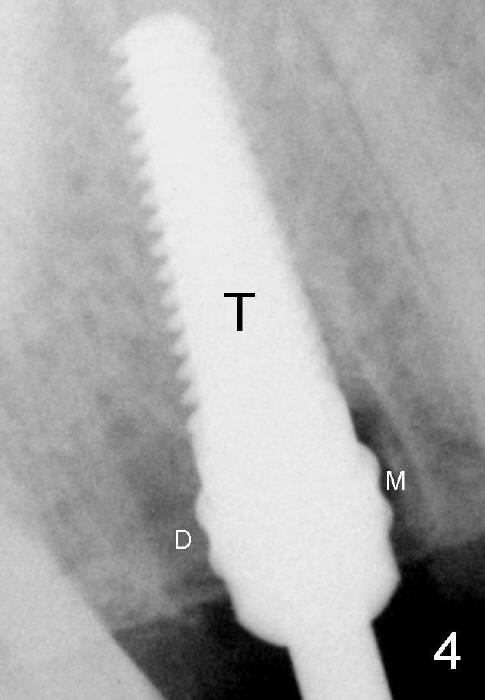

Fig.4: The remaining mesial (M) and distal (D) sockets are lateral to a 4.5x17 mm tap (T).